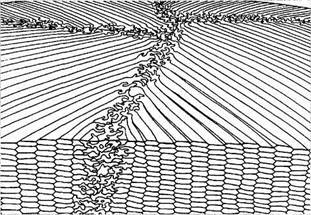

Рис. 3.4.11. Особенности расположения хрусталиковых волокон:

а — схематическое изображение; б — сканирующая электронная микроскопия (по Kuszak, I989)

Волокна хрусталика (fibrae lentis) (рис. 3.4.5, 3.4.10—3.4.12). Переход от эпителиальных клеток герминативной зоны к хруста-ликовому волокну сопровождается исчезновением между клетками «пальцевых вдавлений», а также началом удлинения базальной и апикальной частей клетки. Постепенное накопление хрусталиковых волокон и смещение их к центру хрусталика сопровождается формированием ядра хрусталика. Это смещение клеток приводит к образованию S- или С-подобной дуги (ядерная дуга), направленной вперед и состоящей из «цепи» ядер клеток. В области экватора зона ядерных клеток имеет ширину порядка 300—500 мкм [629].

Расположенные глубже волокна хрусталика имеют толщину 150 мкм. Когда они теряют ядра, ядерная дуга исчезает. Хрусталиковые волокна имеют веретенообразную или ремнепо-добную форму, располагаясь по дуге в виде концентрических слоев. На поперечном разрезе в области экватора они гексагональной формы.

Рис. 3.4.12. Характер расположения хрусталиковых

волокон. Сканирующая электронная микроскопия

(по Kuszak, 1989):

а —плотно упакованные хрусталиковые волокна; б — «пальцевые вдавления»

По мере погружения к центру хрусталика постепенно нарушается их однообразие по размеру и форме. В области экватора у взрослых ширина хрусталикового волокна колеблется от 10 до 12 мкм, а толщина — от 1,5 до 2,0 мкм. В задних частях хрусталика волокна более тонкие, что объясняется асимметричной формой хрусталика и большей толщиной передней коры [621, 624]. Длина хрусталиковых волокон в зависимости от глубины расположения колеблется от 7 до 12 мм [183]. И это при том, что первоначальная высота эпителиальной клетки равняется всего 10 мкм.

Концы хрусталиковых волокон встречаются в определенном месте и формируют швы.

Швы хрусталика (рис. 3.4.13). В феталь-ном ядре имеется передний вертикально расположенный Y-образный и задний инвертированный Y-образный швы. После рождения по мере роста хрусталика и увеличения количества слоев хрусталиковых волокон, формирующих свои швы, происходит пространственное объединение швов с образованием звездоподоб-ной структуры, обнаруживающейся у взрослых.

Рис. 3.4.13. Формирование швов в месте стыка волокон, происходящее в различные периоды жизни:

/ — Y-образный шов, формирующийся в эмбриональном периоде; 2 — более развитая система швов, возникающая в детском периоде; 3 — наиболее развитая система швов, обнаруживаемая у взрослых

Основное значение швов заключается в том, что благодаря такой сложной системе контакта между клетками сохраняется форма хрусталика практически на протяжении всей жизни.

Особенности мембран хрусталиковых волокон. Контакты типа «пуговица — петля» (рис. 3.4.12). Мембраны соседствующих хрусталиковых волокон соединены при помощи разнообразных специализированных образований, изменяющих свое строение по мере смещения волокна с поверхности в глубь хрусталика. В поверхностных 8—10 слоях передних отделов коры волокна соединяются при помощи образований типа «пуговица — петля» («шар и гнездо» американских авторов), распределенных равномерно по всей длине волокна. Подобного типа контакты существуют только между клетками одного слоя, т. е. клетками одного поколения, и отсутствуют между клетками разных поколений. Это обеспечивает возможность передвижения волокон относительно друг друга в процессе их роста.